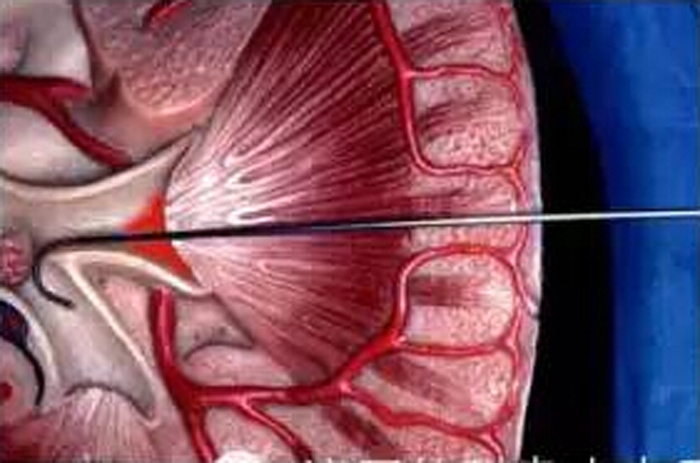

穿刺示意圖

??? 這個(gè)手術(shù)只要不到1厘米大小的切口就能完成,是真正的鑰匙孔手術(shù)。手術(shù)前醫(yī)生要仔細(xì)研究CT片,用抗生素控制尿路感染。手術(shù)時(shí),先在超聲定位下穿刺腎盞,擴(kuò)張建立一個(gè)約0.8厘米大小的通道,然后置入腎鏡,直視下用鈥激光、氣壓彈道或EMS超聲碎石系統(tǒng)將結(jié)石擊碎,并吸出體外。手術(shù)結(jié)束,需要放置腎造瘺管和輸尿管支架管起到外引流和內(nèi)引流作用。腎造瘺管一般術(shù)后1周拔了就可以出院,中途需要來(lái)復(fù)查尿常規(guī)。一般一個(gè)月后來(lái)院,通過(guò)膀胱鏡下拔出輸尿管支架管。泌尿外科自2014年購(gòu)置了最先進(jìn)的瑞士第五代EMS超聲碎石清石系統(tǒng),大大縮短了手術(shù)時(shí)間,減少了手術(shù)并發(fā)癥,每年開(kāi)展手術(shù)100多臺(tái),技術(shù)達(dá)到了省內(nèi)先進(jìn)水平。另外這個(gè)手術(shù)偶爾也可能會(huì)出現(xiàn)一定的并發(fā)癥,如大出血是比較嚴(yán)重的并發(fā)癥。這個(gè)時(shí)候就需要在放射科介入室行超選擇腎動(dòng)脈栓塞止血術(shù)(一種微創(chuàng)手術(shù)),衢州市人民醫(yī)院在衢州地區(qū)最早開(kāi)展介入手術(shù),所以此手術(shù)的成功開(kāi)展,也需要醫(yī)院強(qiáng)大的綜合實(shí)力作為保障。